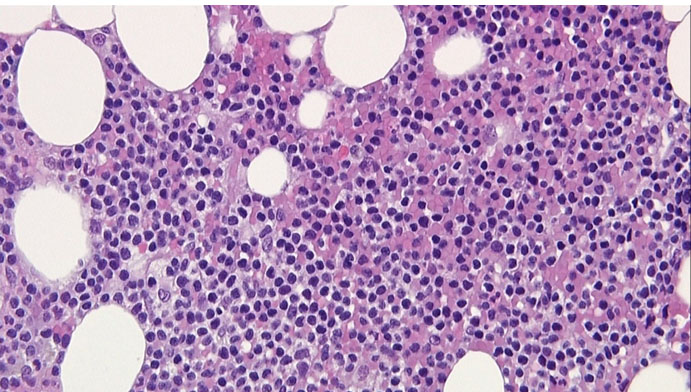

In view of the clinical picture of a non-resolving skin lesion with lymphocytosis, a diagnosis of possible T-cell malignancy was made. A flow cytometry showed 90% atypical T-cells with positive CD45, CD2, CD3, CD4, CD5, CD7, and CD52 (Figure 3). A bone marrow biopsy showed 50–80% cellularity with atypical lymphoreticular infiltrate (Figure 4), and immunochemistry was consistent with flow cytometry findings. Immunoperoxidase stain for CD16, CD25, CD30, CD56, CD117, CD1a, and TdT were negative, and clonal T-cell receptor (TCR) beta gene rearrangement tests were positive. The bone marrow biopsy also showed an abnormal male karyotype 47XY, +8 [2]/46,XY [3] suggestive of Trisomy 8. A computed tomography (CT) scan revealed splenomegaly (15 cm) and diffuse lymphadenopathy (supraclavicular, hilar, axillary, inguinal, mediastinal). The patient was diagnosed with T-PLL and transferred to a leukemia center to receive treatment.

Figure 4: Bone marrow biopsy; 80% cellularity with atypical lymphoreticular infiltrate.

T-cell prolymphocytic leukemia is a rare but aggressive mature T-cell malignancy that accounts for less than 2% of mature lymphocytic leukemias and has a poor prognosis [2]. It is usually encountered in adults >65 years or older, with a 2:1 male to female ratio [3]. T-cell prolymphocytic leukemia can present with fatigue, splenomegaly (>80%), lymphadenopathy (50%), skin lesions (<30%), leukocytosis (70%) [2],[4],[5]. Skin lesions can include skin nodules, maculopapular rash, or erythroderma and can predate the leukocytosis [6]. Like in our case, T-PLL may be misdiagnosed as eczema or fungi especially if this is the only presenting symptom. Patients often have a white cell count >100,000/μL and a hemoglobin of 10 g/dL at presentation [2]. Peripheral smear generally shows a classic prolymphocytic morphology with smallto-medium-sized cells, high nuclear/cytoplasmic ratio, a prominent nucleolus with a condensed chromatin, and basophilic cytoplasm with blebs. This may differentiate T-PLL from T-cell large granular lymphocytic leukemia which have usually large lymphocytes with azurophilic granules [1]. T-cell prolymphocytic leukemia cell nuclei may be regular round or oval, or they may be irregular and convoluted. However, in a few cases, the cells may be small or cerebriform and indistinguishable from chronic lymphocytic leukemia (CLL) cells, and the nucleolus may not be visible under light microscopy, hidden by the dense chromatin. Flow cytometry and immunohistochemistry are diagnostic (T-cell markers +) with characteristic clonal TCR gene rearrangement [1],[7]. T-cell prolymphocytic leukemia is often TdT-, CD1a-, CD2+, CD5+, CD7+, CD16-, CD56-, with variable CD4 and CD8 expression. In all cases of T-PLL, TCR b and/or g chain genes are rearranged. Most T-PLL cases express high densities of CD52, which is a glycosylphosphatidylinositol-linked protein present on both normal and malignant lymphocytes and is a frequent therapeutic target for T-PLL [1],[2],[3]. CD7 positivity differentiates T-PLL from other mature T-cell leukemias. Likewise, T-PLL and B-PLL are differentiated by the presence of lymphadenopathy, skin involvement, and immune histochemistry in T-PLL [1]. Bone marrow biopsy shows prolymphocyte infiltrates with a mixed diffuse and interstitial pattern and reticulin fibrosis. Skin biopsy may show perivascular, periadnexal, or diffuse dermal infiltrates with irregular medium-sized lymphocytes without epidermotropism [1]. Tissue biopsy, such as splenic biopsy, demonstrating red pulp infiltration may be necessary in patients with unusual presentation [3]. Similar to our case, T-PLL may be associated with chromosomal aberrations mainly chromosomes 14, 8, 11, and X [8], which may explain its aggressiveness. The prognosis of T-PLL is poor with a median survival rate of seven months with conventional chemotherapy [1],[3]. Anti-CD52 monoclonal antibody is the first line of treatment (improves survival from 6 to18 months). Patients often need allogeneic stem cell transplantation, and this can extend survival to four years [1].